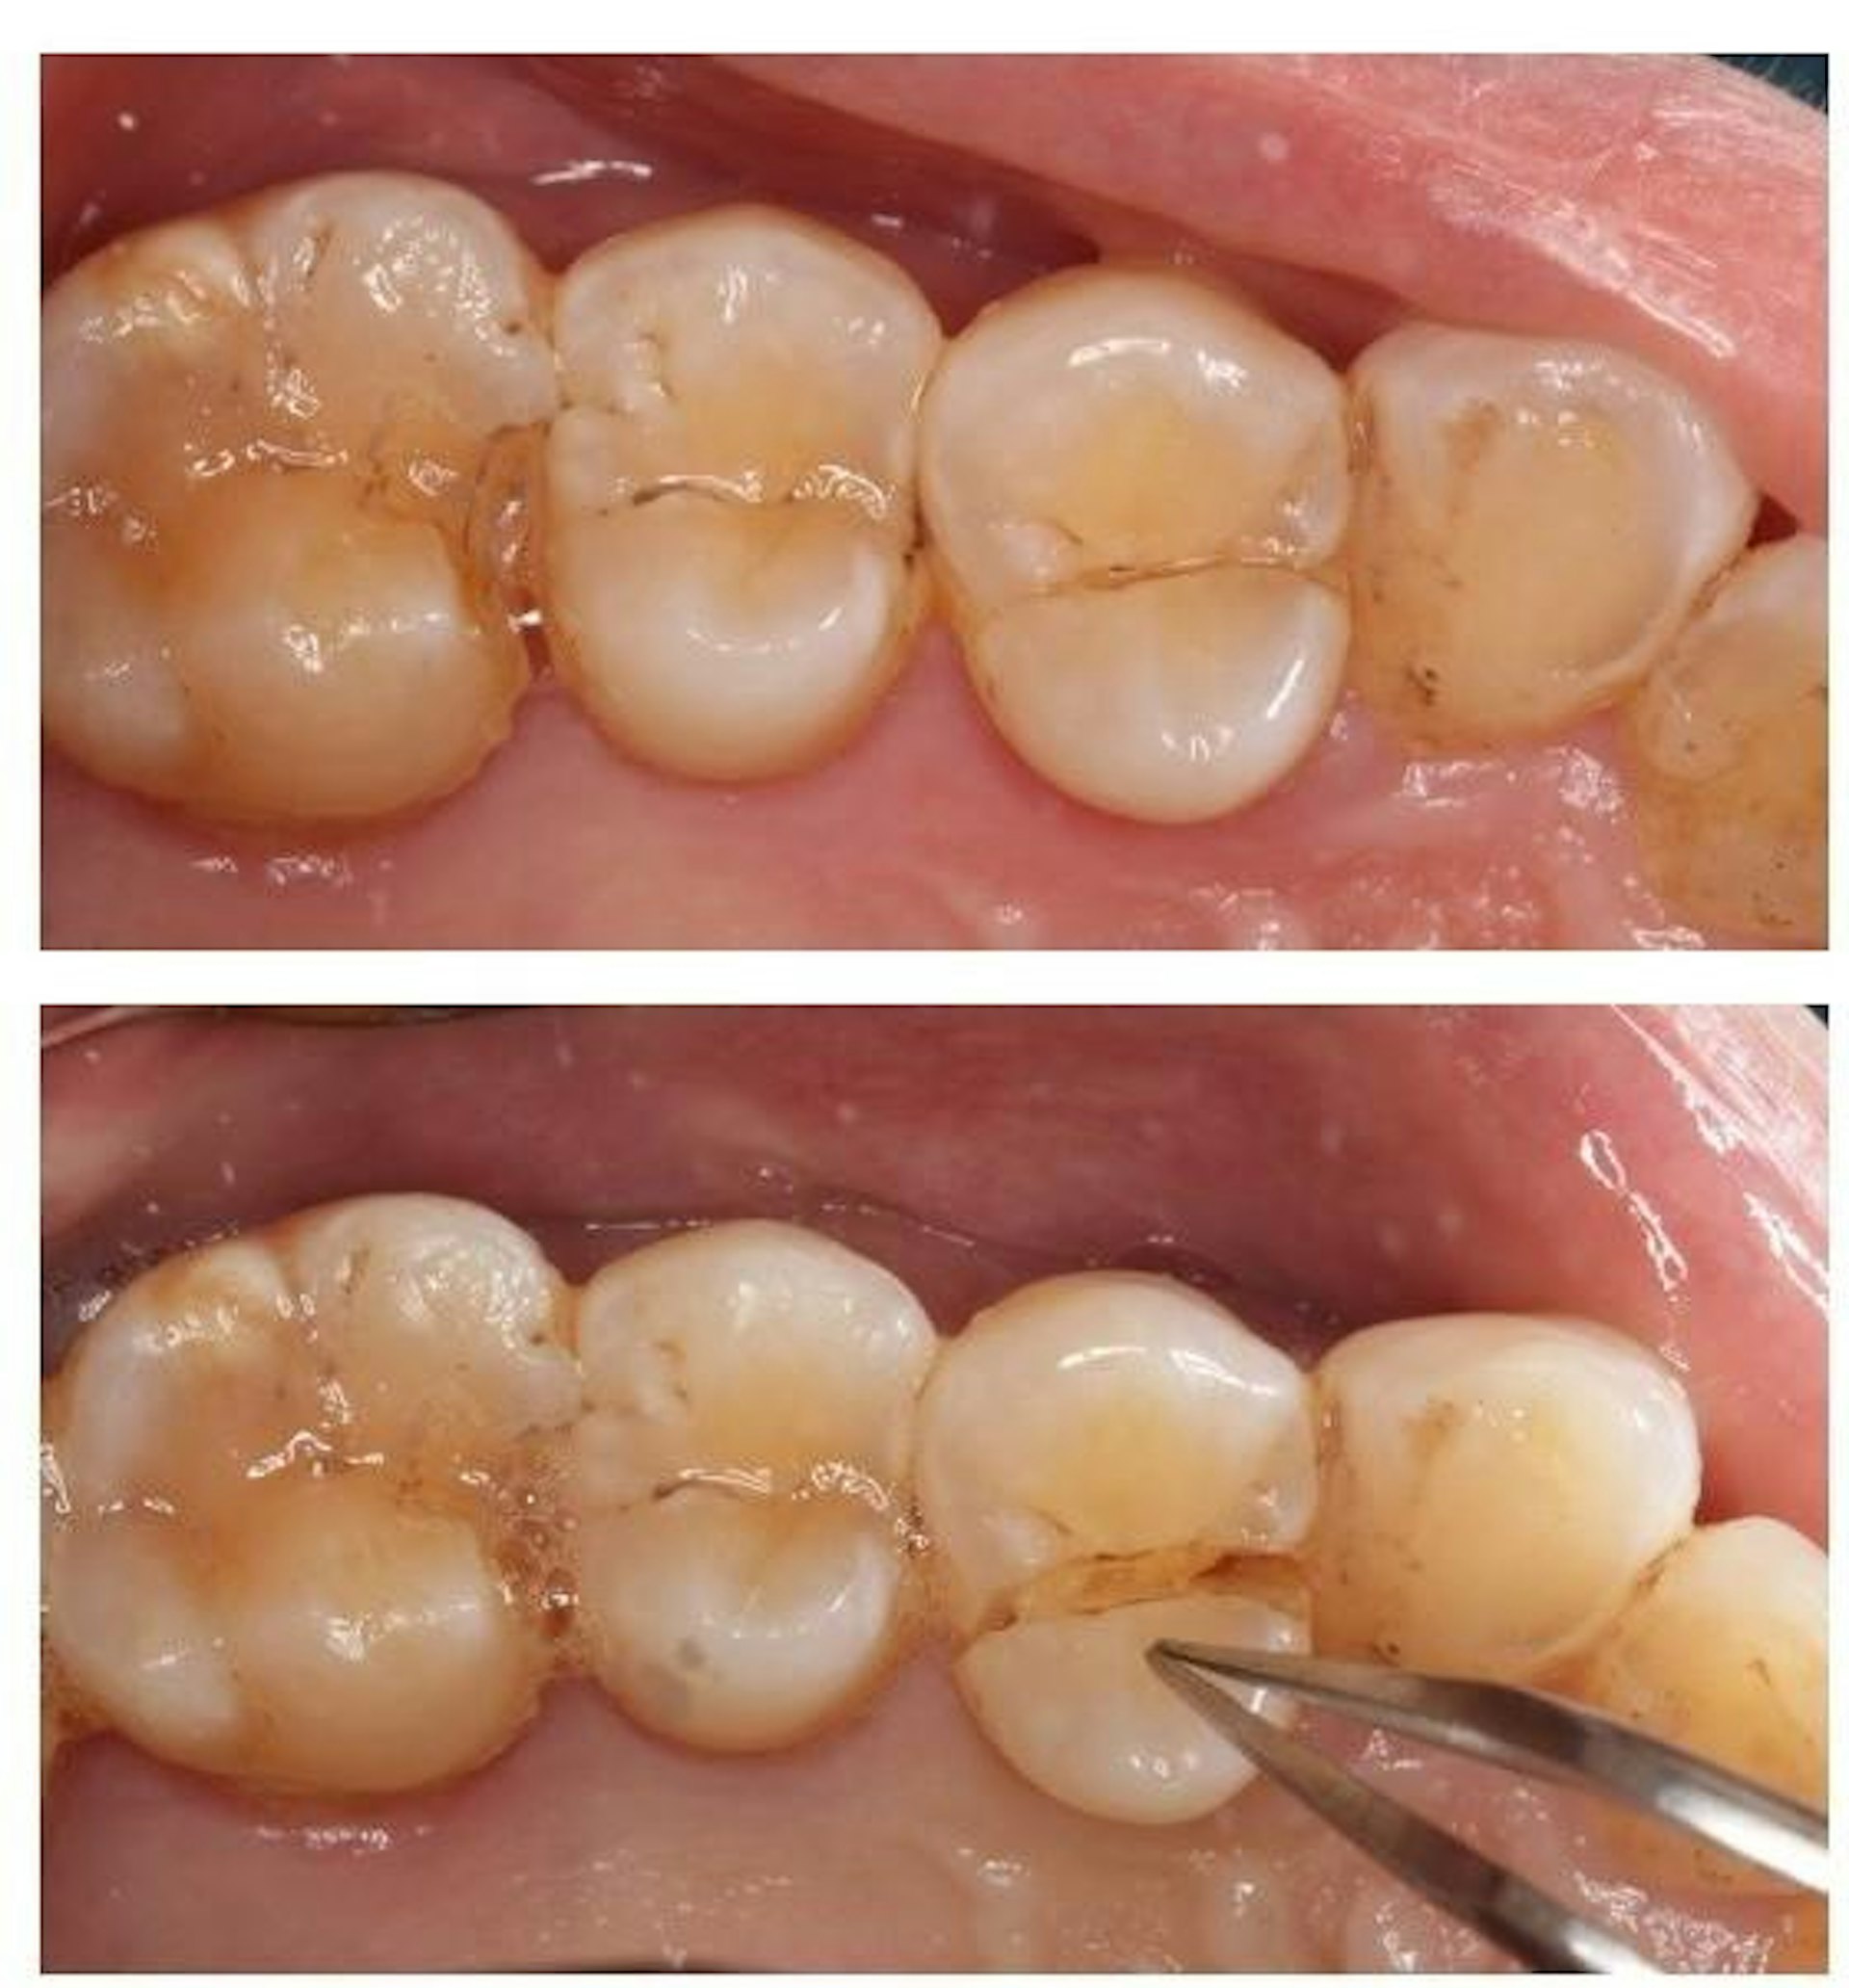

當牙醫懷疑病人牙齒有裂,會進行不同的詳細檢查。例如先以排除法檢查相關牙齒有否蛀牙或牙周病等其他問題,再慢慢收窄範圍,接着以咬合測試(Bite test)或透照法檢查 (Transillumination),嘗試找出裂牙所在位置。

牙醫會以照X光片和臨床病徵,判斷裂牙的術後情況(Prognosis),與病人討論不同的治療方案。舉例當牙齒裂紋並沒有裂愈深,裂向牙房神經線,而剩餘的牙齒結構完整,牙醫會嘗試以補牙物料或牙套修復及保護牙齒。但如果裂紋已經深入牙房神經線,就有需要先進行根管治療,然後才可進行修復。再者,如果裂紋已裂到牙齒深處,例如裂到牙肉以下或者牙房底部,情況便不容樂觀,牙醫會與病人討論牙齒的去留,可能有需要拔牙。